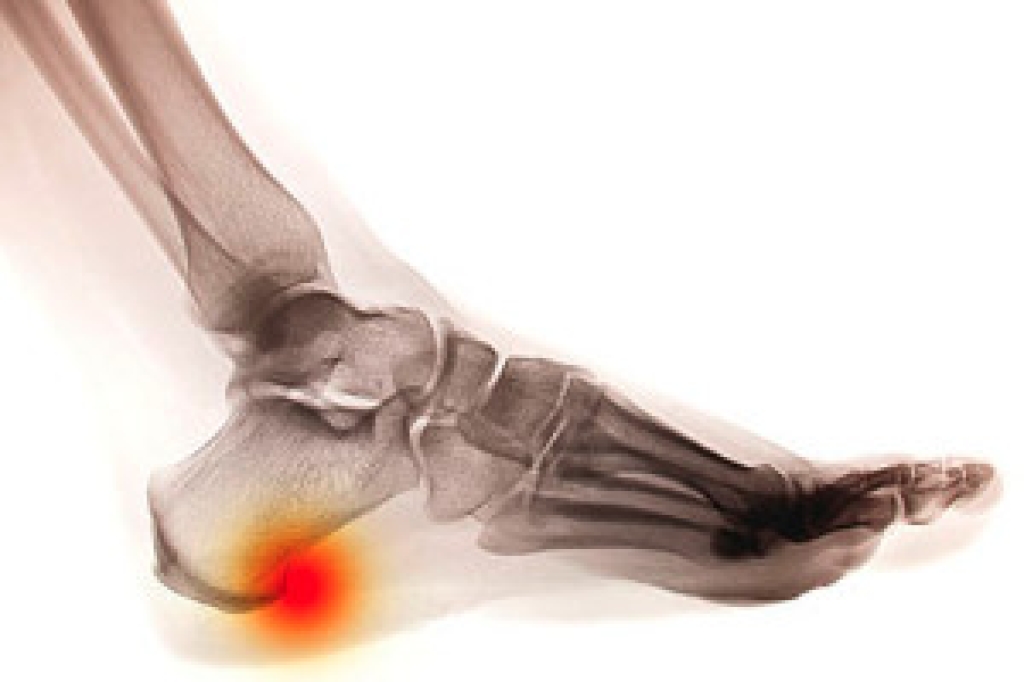

The symptoms may be similar in sprained and broken toes, and it may be difficult to determine the extent of the injury. If the bone is intact, it is most likely a sprained toe, and one or more broken bones are indicative of a fractured toe. There are several symptoms that are associated with broken toes, including severe discomfort and pain beginning at the time of the injury, bruising on the toe and surrounding area, in addition to the inability to walk and put weight on it. Two common causes for broken toes to occur may include stubbing it against something hard or dropping a heavy object on it. Once a proper diagnosis is performed, which typically consists of having an X-ray taken, it will be confirmed if the toe is broken. At this time, the correct treatment procedure can begin, which will generally include resting the toe, and splinting it to the toe next to it, which may aid in stabilizing it. If you feel you have broken your toe, it is recommended that you speak to a podiatrist as quickly as possible, so a proper diagnosis can be determined.

Although most people try to avoid foot trauma such as banging, stubbing, or dropping heavy objects on their feet, the unfortunate fact is that it is a common occurrence. Given the fact that toes are positioned in front of the feet, they typically sustain the brunt of such trauma. When trauma occurs to a toe, the result can be a painful break (fracture).